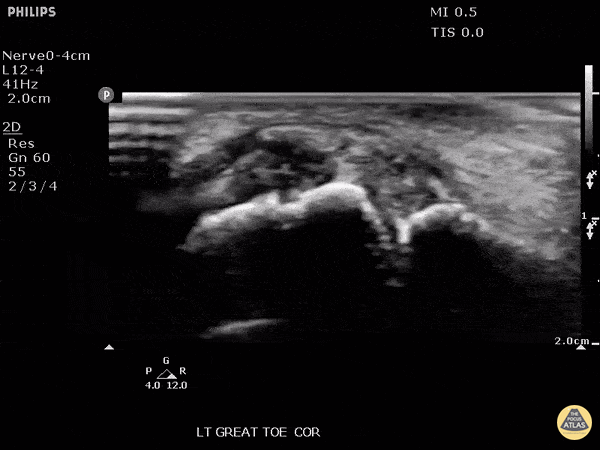

Patient presented with great toe pain. POCUS performed and detected effusion in first metatarsophalangeal joint. Eventually determined to be monosodium urate crystals as seen in gout. Image courtesy of Robert Jones DO, FACEP @RJonesSonoEM Director, Emergency Ultrasound; MetroHealth Medical Center; Professor, Case Western Reserve Medical School, Cleveland, OH View his original post here